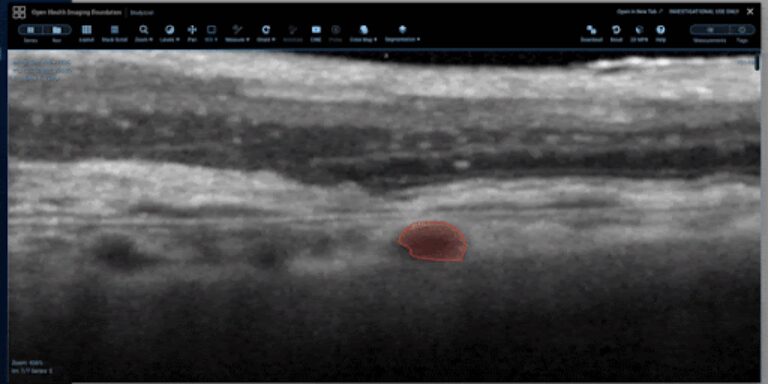

As shown below, the viewer supports an open freehand tool for retinal layer tracing, a closed freehand ROI tool for capturing distinct findings, such as intraretinal fluid pockets, and a sculpt tool for precise editing of freehand ROIs.

Sculpt tool for precise editing of freehand ROIs.